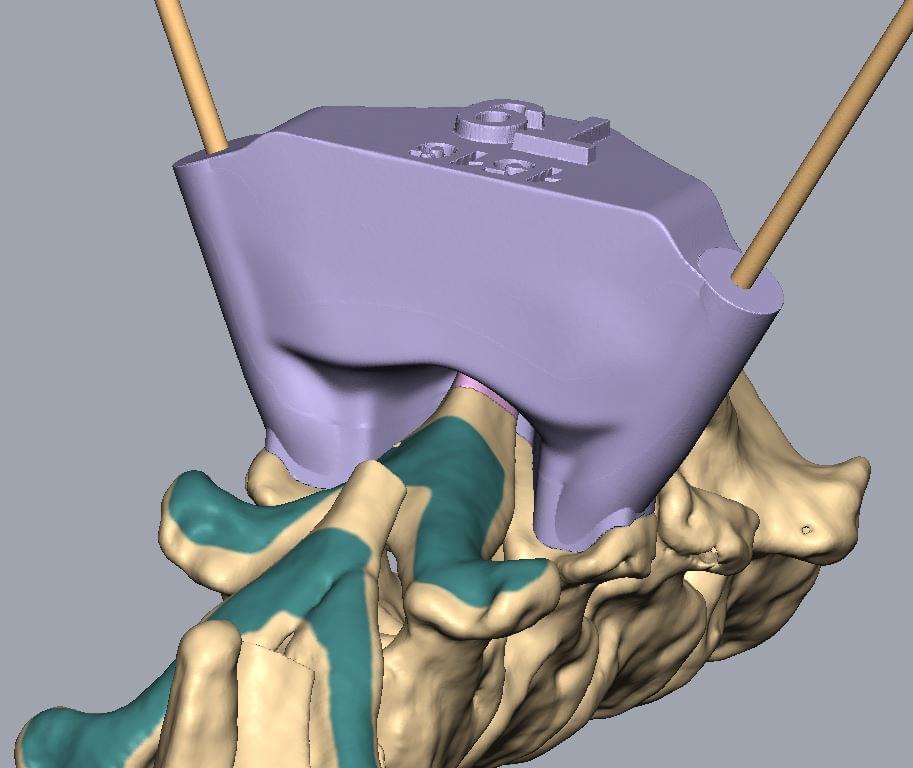

Veterinární chirurgové se učí od chirurgů lidských. Postupy aplikované na humánního pacienta se adaptují na pacienta zvířecího. Veterinární neurochirurgové umí odstranit nádor z mozku, operovat vyhřezlý meziobratlový disk, stabilizovat nestabilní páteř pomocí 3D tištěných operačních šablon.

Počítačové plánování stabilizační spinální chirurgie

Lumbosakrální spinální stabilizace

Jedny z nejnáročnějších operací jsou zákroky na deformované páteři francouzských buldočků a mopsů. Vyžadují předchozí CT a MRI vyšetření, speciální 3D tištěné vrtací šablony pro bezpečné usazení implantátů a v zásadě vytvoření nové podpůrné páteře z polymetylakrylátu (kostní cement). Takové zákroky trvají i několik hodin a vyžadují extenzivní plánování a maximální soustředění celého operačního týmu během celého zákroku.